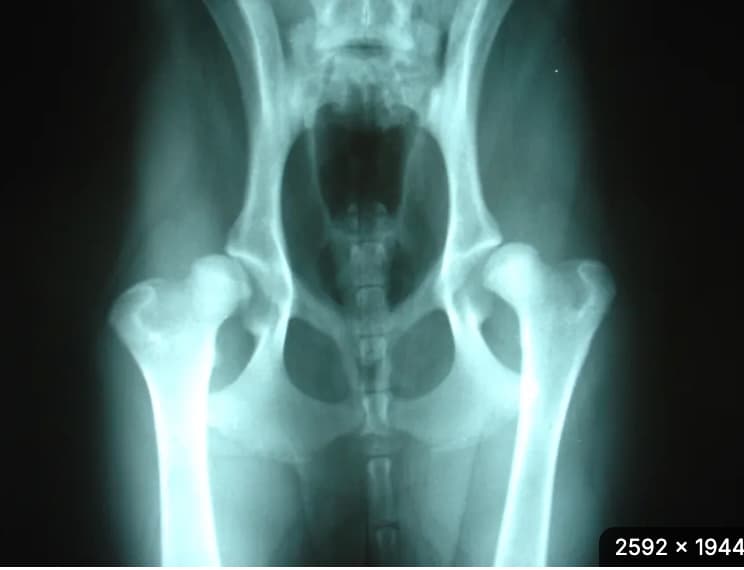

Hip Dysplasia

A Number of Environmental Factors Can Affect the Incidence of Hip Dysplasia in Dogs ScienceDaily (Mar. 26, 2012) — Hip dysplasia (HD) in dogs is affected to a larger degree than previously believed by the environment in which puppies grow up. It is particularly during the period from birth to three months that various environmental factors appear to in...